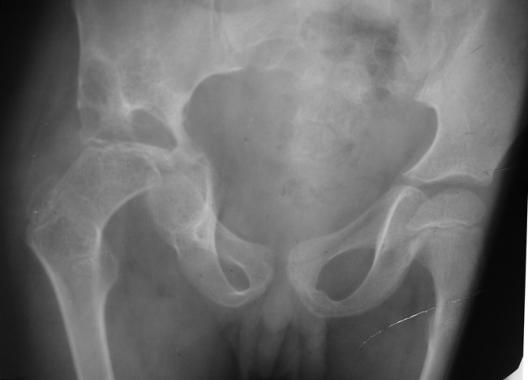

髋关节脱位(股骨和骨盆髋臼之间的关节失去了正常位置)

1.脱位原因:高能量损伤才能脱位,车祸、高坠伤等,发生率约占全身各关节脱位的5%,85%-90%为后脱位,多发生于青壮年

2.脱位分型:以髂坐线(Nelaton:坐骨结节至髂前上棘的连线。正常情况下,此线经过大转子尖端,当股骨颈骨折或髋关节后脱位时,大转子尖端可向上移位超过此线。)为标准:前方——前脱位(外展位);后方——后脱位(内收位);中心脱位:股骨头突破髋臼底部或入盆腔(合并有髋臼横行骨折,或髋臼顶骨折或者髋臼复杂性骨折,并入髋臼骨折处理)

3.临床表现:1、外伤史,2、肿胀、疼痛、髋关节活动受限,后脱位:患者缩短;髋关节屈曲、内收、内旋(弹性固定),黏膝征(+),前脱位:患肢增长;髋关节屈曲、外展、外旋(弹性固定),黏膝征(-),中心性脱位:股骨头严重移位者,大粗隆内移,患肢短缩。

坐骨神经损伤

4.治疗:新鲜髋关节后脱位,应立即施行手法复位,即使合并髋臼或股骨头骨折者,亦应即刻复位,闭合复位仅可尝试1或2次一旦失败,则应行切开复位,以防对股骨头进一步损伤。闭合复位常用方法:AIlis手法复位,Stimson重力复位法

对陈旧性脱位多主张手术切开复位.

5.并发症:1、股骨头缺血坏死,2、创伤性关节炎,3、术后再脱位